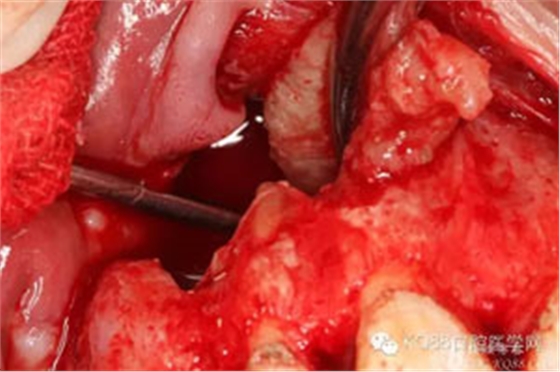

圖7.囊壁被完整摘除后遺留的巨大骨腔,11根尖牙膠尖依稀可見。

圖9.11/12/13的牙根完全裸露在囊腔內(nèi),13根尖牙膠尖超填過(guò)多。

圖10.超聲骨刀行11/12/13根尖切除術(shù)